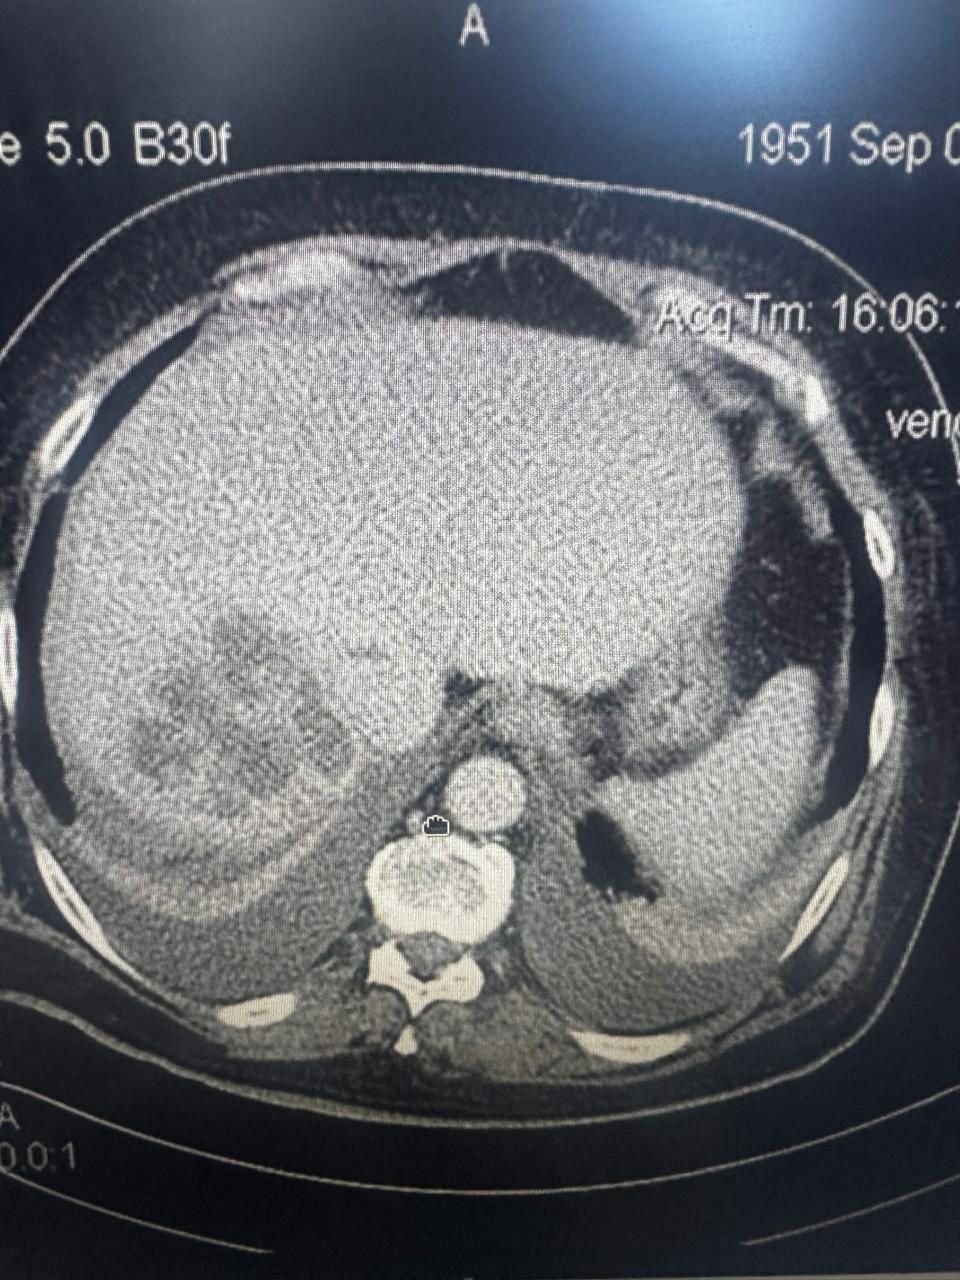

PrimaMedia, 26 ноября. Жителя Приморья экстренно доставили в больницу Владивостока с острой болью, где врачи обнаружили у него кисту размером с целый орган. Хирургам удалось спасти 53-летнего пациента и избежать сложной полостной операции, сообщила пресс-служба Минздрава Приморья.

"Под местной анестезией, под контролем УЗИ мы выбрали оптимальную точку доступа, установили дренаж и эвакуировали около двух литров жидкости из кисты. Затем ввели склерозирующие препараты — они позволяют “склеить” полость и избежать повторного заполнения", — приводит пресс-служба слова руководителя отделения общей хирургии Игоря Кондрашова.

Отмечается, что благодаря малоинвазивной методике пациенту удалось избежать обширных разрезов и длительного периода восстановления. Уже через несколько дней наблюдения в стационаре мужчина сможет вернуться к нормальной жизни.